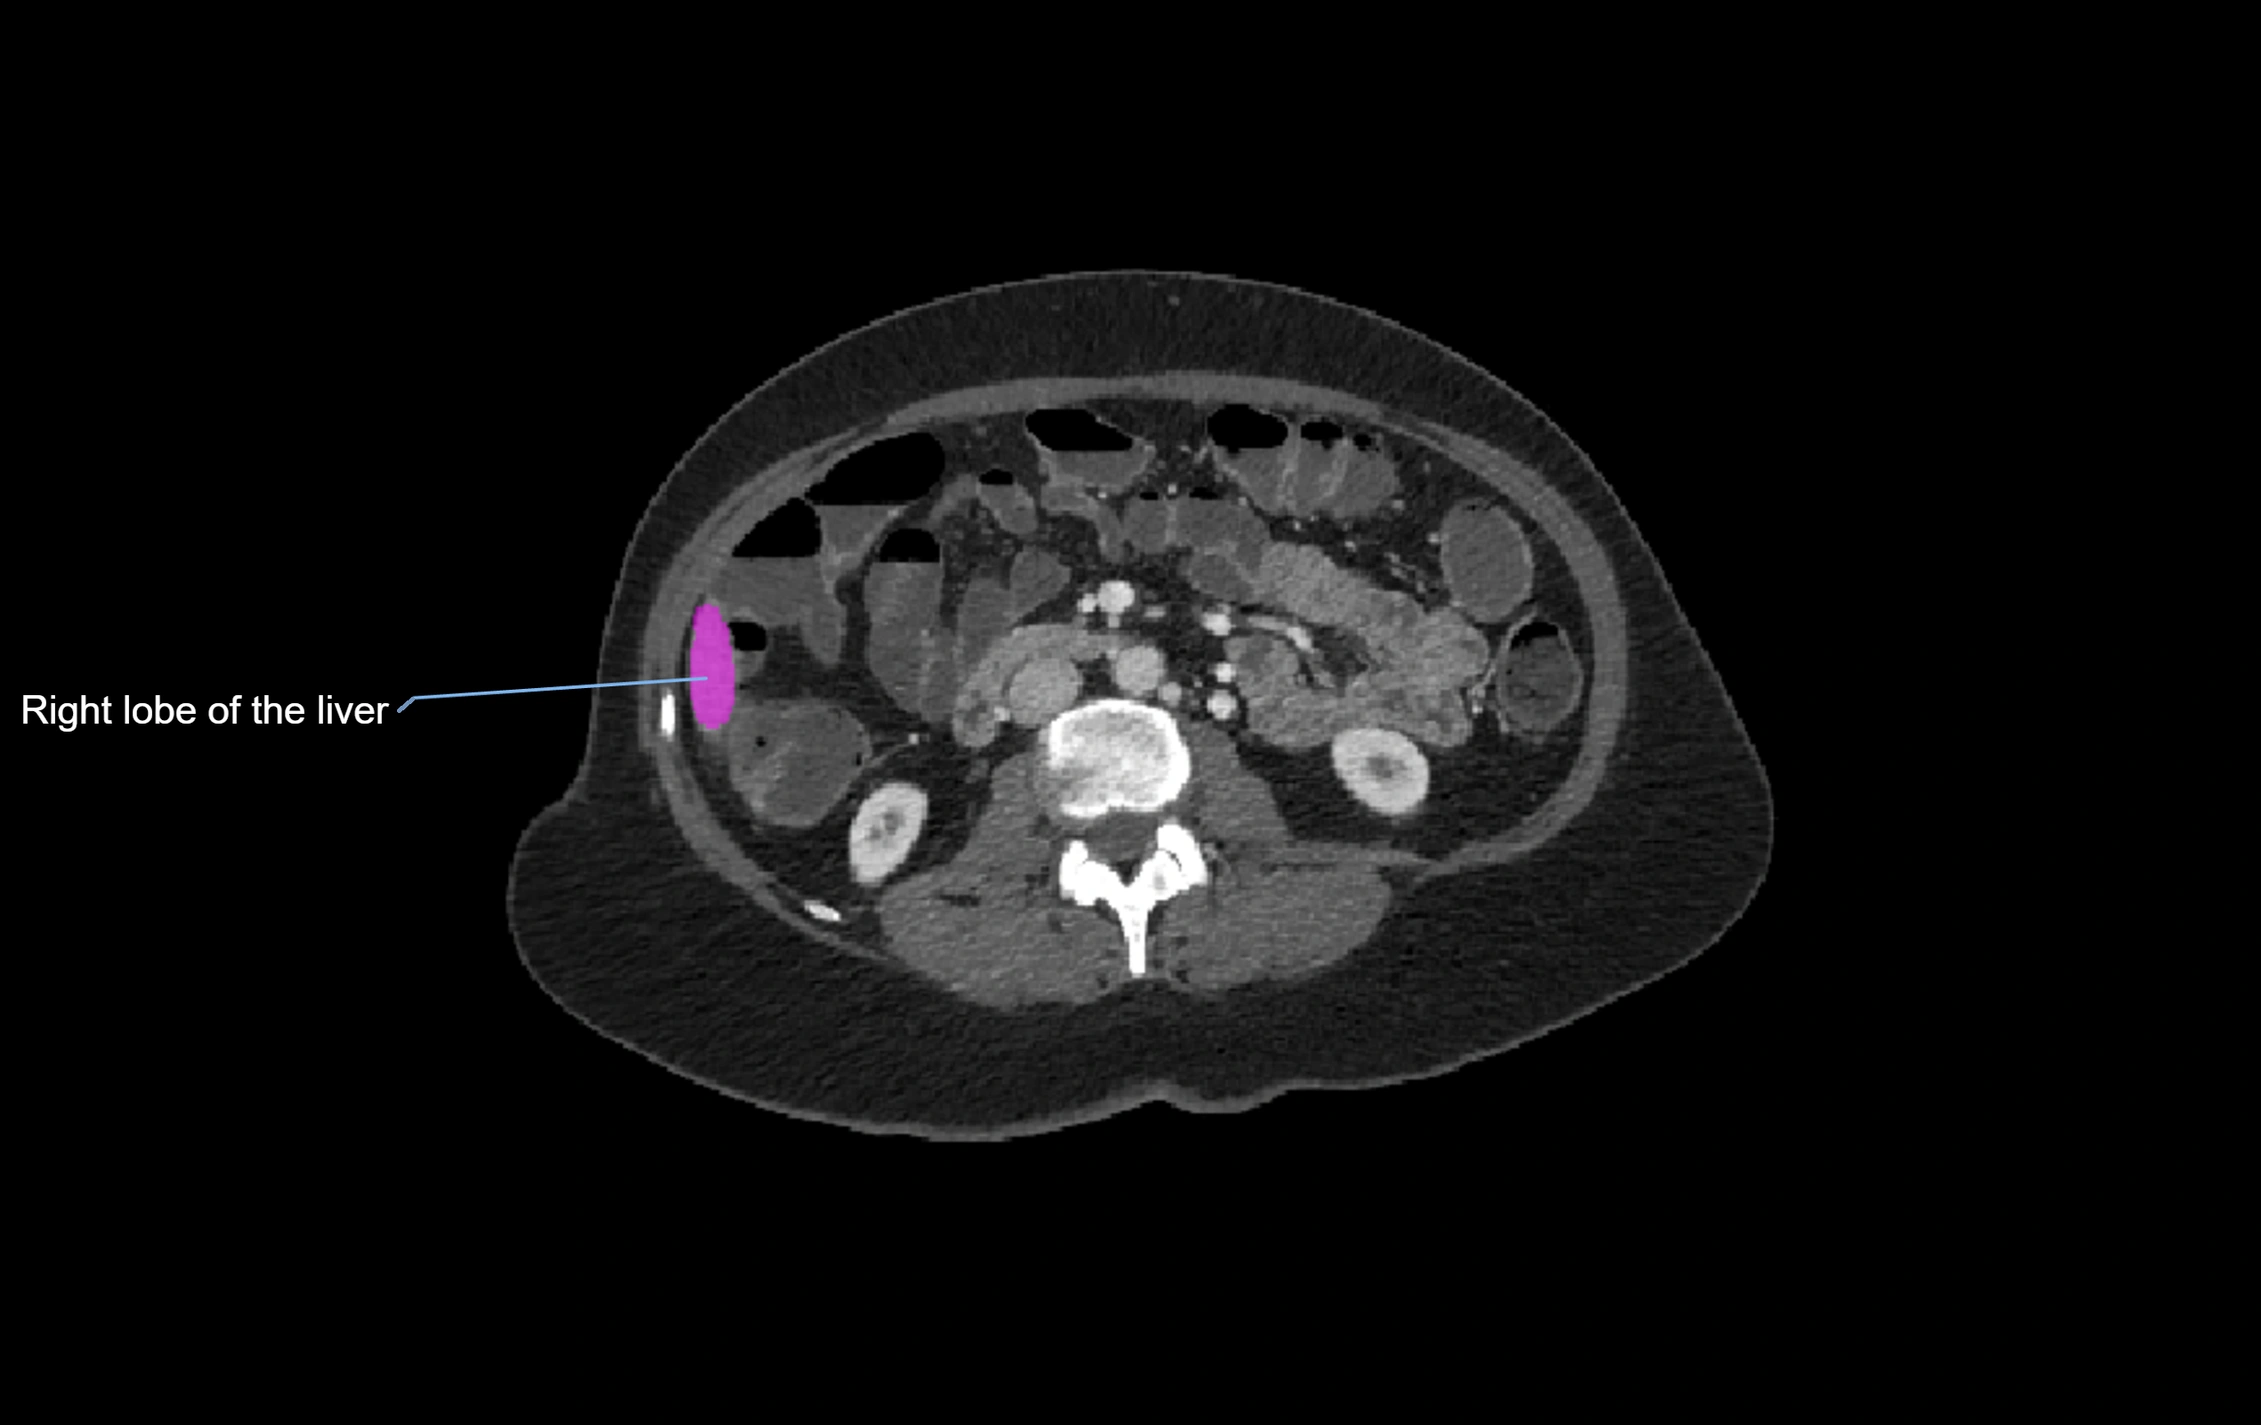

CT Image

image